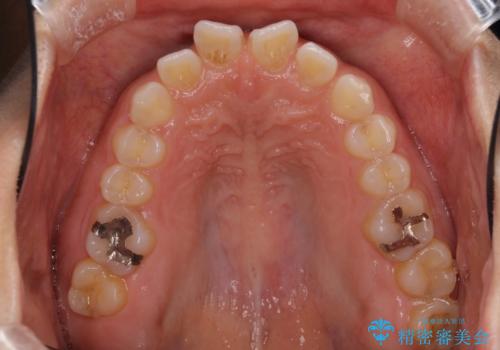

隙間の空いた前歯を閉じたい インビザライン矯正

- 前歯の隙間を気にして来院された患者様です。

隙間、捻転ともに軽微でありましたが、下顎前歯の突き上げにより隙間ができていたため、インビザラインを用いて咬み合わせを改善しながら前歯の歯列を整えていくこととしました。

当初は1年程度で終えられると思いましたが、治療途中から装着時間が短くなったり、来院間隔が長期になったりとし、結果として4年半以上の治療期間となりました。

治療途中に上顎前歯は失活してしまいましたが、変色が顕著ではないため、経過を見ていくこととなりました。